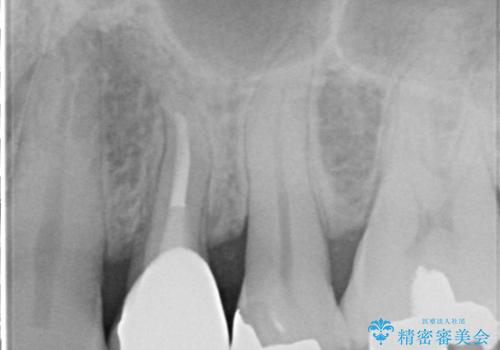

- 歯肉の下まで深く歯が折れたことを主訴に来院された患者様です。

かかりつけ医にて応急的に修復してますが根本的な治療を希望され、矯正的挺出を行ったのち、歯周外科を行い、歯冠修復をしております。

歯肉縁下の水平破折をきちんと治療するためには時間も費用もかかります。